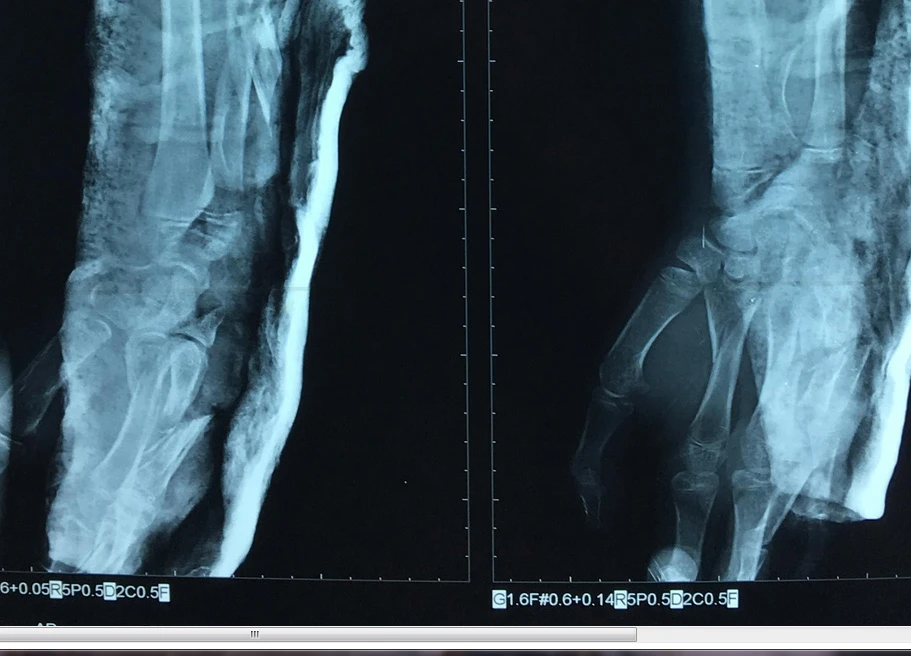

Tiếp theo, các BS nắn trật chỏm quay, cố định chỏm quay bằng kim. Đồng thời kết hợp xương dọc trục xương trụ, bắt vít cố định mỏm khuỷu, nắn xuyên kim cố định cổ tay, xương bàn ngón 4 và 5 tay trái.

Tay trái bệnh nhi T. sau khi phẫu thuật. Ảnh: VÕ KHÁNH